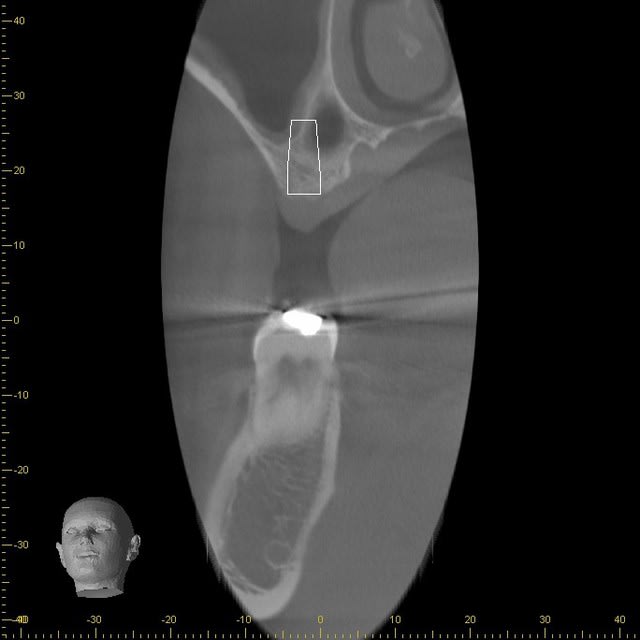

Voila ce que cela donne avec un implant de diamètre 4mn

A1 wgdijm - Eugenol